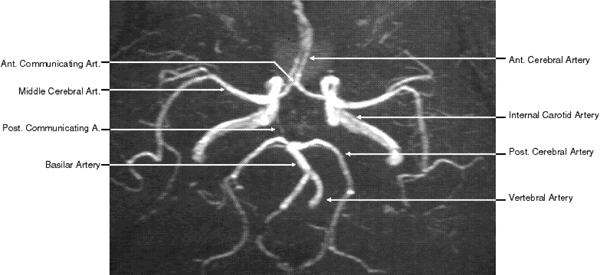

With 2D TOF, multiple thin imaging slices are acquired with a flow-compensated gradient-echo sequence. Slice thickness is limited to 1.5 mm. These images can then be combined by using a technique of reconstruction such as maximum intensity projection (MIP) to obtain a 3D image of the vessels analogous to conventional angiography (Fig. 11). The 2D TOF MRA technique is robust and relatively fast; it may be adequate for screening, but it is less accurate for gauging the degree of stenoses.

Fig. 11. Two-dimensional time-of-flight magnetic resonance angiography of the circle of Willis (superior view).

MRA offers several advantages over conventional angiography and digital subtraction angiography.41 MRA is a noninvasive technique, avoiding the need for injection of contrast media into the bloodstream. This makes MRA a safer procedure, avoiding risks such as stroke, arterial injury, bleeding, hypersensitivity reaction, renal complications, or any other complication related to the placement of the probe or injection of the contrast media. With MRA no ionized radiation is used; therefore, multiple view angles can be used without additional risk to the patient. The radiologist can rotate the image in any desired angle, choosing the optimal view of the area of interest. MRA can also be combined with MRI, adding only 10 to 15 minutes to the total imaging time. MRA enables gathering of information regarding the parenchyma and the flow in a single examination, making it less costly in many instances. Finally, MRA can also provide hemodynamic data regarding blood flow in addition to the vascular morphology.

However, MRA has several limitations. The main one is limited spatial resolution compared with conventional angiography. In addition, a variety of artifacts may arise because of problems related to the distribution of velocities in the vessel. Examples include signal loss with turbulent flow at areas of stenoses, leading to overestimation of the degree of stenoses; loss of signal at vessels adjacent to brain-air interface (parasellar area); and motion artifacts due to swallowing.